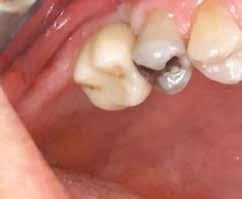

2–5. ábra: A metszések és a deepitelizáció. – 6–9. ábra: Félvastag lebeny. – 10. ábra: A nyelezett ínylebeny „bepróbálása”.

horizontális metszéssel kötöttük össze (2–5. ábra). A metszések hosszát és a köztük lévő távolságot minden esetben a lágyszövet augmentációhoz szükséges keratinizált szövet határozza meg. A lebeny deepitelizációját egy 15C-s szikepengével végeztük (6. ábra). Ezt követően félvastag lebenyt preparáltunk (7. ábra). A lebenyt apikálisan, az alapjáról belső, felületes metszéssel felszabadítottuk, hogy passzívan áthelyezhessük és rögzíthessük, feszülés nélkül. Meziális irányba 180 fokkal átforgattuk (8–9. ábra). A meziális papillát alagúttechnikával (tunnelling technique) készítettük elő a graft befogadására (10. ábra). Az így kialakított lebenyt a recipiens ágyban rögzítettük az újonnan kialakított vesztibulum alapjánál 5-0 nem felszívódó PTFE (Coreflon, IMPLACORE) varratokkal. A graftot behajtottuk az ínyszél alá és meziális oldalon rögzítettük PTFE varratokkal (11–14. ábra)

A műtétet követően napi kétszeri, 0,12%-os klórhexidin tartalmú szájvízzel történő öblögetést javasoltunk a páciensnek, két héten keresztül. Gyulladáscsökkentésre 8 óránként 400 mg Ibuprofént javasoltunk, három napon keresztül. A páciens elmondása szerint sem fájdalmat, sem különösebb diszkomfortot nem tapasztalt. Ezt követően, további 4 héten keresztül, 0,2%-os klórhexidin tartalmú szájvízzel történő öblögetést javasoltunk a betegnek és instruáltuk, hogy lehetőleg ne mossa fogkefével az érintett területet. A varratokat egy héttel később távolítottuk el. A donor és a recipiens terület – 10 nappal a műtétet követően – kiválóan gyógyult (15–16. ábra). Az ezt követő kontrollokat a következő időpontokban ejtettük meg: kettő, illetve négy héttel a műtét után, majd három, hat és tizenkét hónappal később, ezt követően pedig félévente (17–20. ábra). Minden kontroll alkalmával professzionális fenntartó kezelést végeztünk a területen.